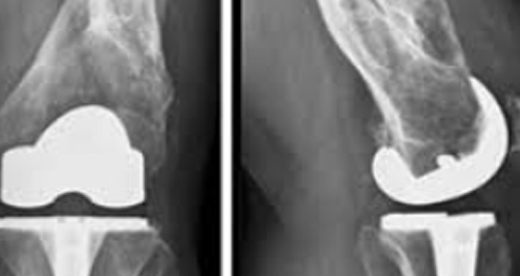

활액막염 인공관절 치환술

외상 또는 질병으로 심하게 손상된 관절을 새로운 관절로 바꿔주는 수술입니다.